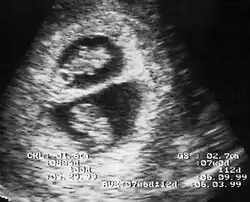

By performing an obstetric ultrasound at a gestational age of 10–14 weeks, monochorionic-diamniotic twins are discerned from dichorionic twins. The presence of a "T-sign" at the inter-twin membrane-placental junction is indicative of monochorionic-diamniotic twins (that is, the junction between the inter-twin membrane and the external rim forms a right angle), whereas dichorionic twins present with a "lambda (λ) sign" (that is, the chorion forms a wedge-shaped protrusion into the inter-twin space, creating a rather curved junction).[4] The "lambda sign" is also called the "twin peak sign". At ultrasound at a gestational age of 16–20 weeks, the "lambda sign" is indicative of dichorionicity but its absence does not exclude it.[5]

In contrast, the placentas may be overlapping for dichorionic twins, making it hard to distinguish them, making it difficult to discern mono- or dichorionic twins on solely the appearance of the placentas on ultrasound.